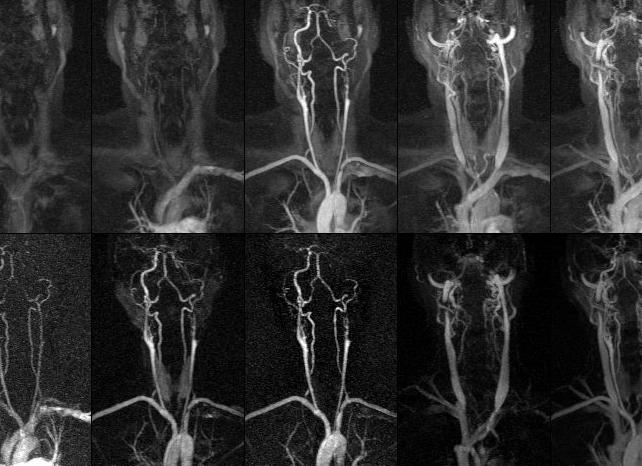

Магнитно-резонансная ангиография считается самым информативным методом исследования, позволяющая создать трехмерную картинку выбранной области, в данном случае сосудов шеи. Метод основан на явлении ядерно-магнитного резонанса: атомы водорода, содержащиеся в тканях, возбуждаются и выделяют энергию, которую фиксирует аппарат, преобразовывая ее в точное изображение. С помощью МРТ можно сканировать ткани человека при помощи тонких срезов и различных плоскостей, что позволяет диагностировать мельчайшие патологии на ранних стадиях развития.

МР-ангиография – вид исследования, который предпочтительнее применять при исследовании сосудов шеи. В отличие от УЗИ, метод визуализирует даже мелкие аномалии.

Магнитно-резонансная ангиография сосудов шейного отдела позвоночника является самым точным методом, лучше визуализирует мелкие патологии и назначается для детального обследования имеющихся нарушений. Чаще всего она назначается для решения спорных клинических ситуаций, в тех случаях, когда другие методы обследования оказались неинформативны.

Магнитно-резонансная томография сосудов шеи или ангиография — это один из новейших методов диагностики позволяющий получить подробную информацию о состоянии сосудов. Исследование проводится на специально оборудованных томографах с мощностью не менее 0,3 тесла. Зачастую ангиография проводится для визуализации сосудов шеи и головного мозга, это наиболее тяжело диагностируемая зона, поэтому МРТ — это идеальный метод. Магнитно-резонансная томография сосудов шеи помогает поставить точный диагноз, а также является неотъемлемым этапом в планировании оперативного вмешательства на органах шеи.

Правильно выполненная магнитно-резонансная томография сосудов шеи поможет с точностью диагностировать различного рода заболевания и оценить патофизиологические физико-химические процессы. Благодаря томографии можно оценить изменения интенсивности течения крови в сосудах, определить очаги воспалительного процесса, а также оценить окружающие исследуемую область ткани и вторичные патологии, которые развиваются вследствие нарушения кровоснабжения.